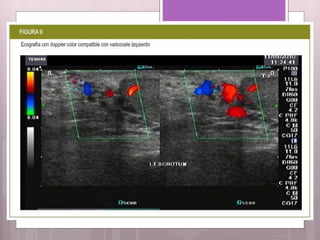

• #13 Ecografia: Es el método más usado pero no proporciona una evaluación cuantitativa. ( FIGURA 8 )

• #14 La aparición del Eco-doppler color nos permite determinar y medir tanto la dirección como la velocidad de caudal sanguíneo ( FIGURA 9 ). El testículo es observado con gran detalle mediante esta técnica. La conservación de las imágenes obtenidas nos permitirá un seguimiento comparativo con las que obtengamos después del tratamiento.  Se realiza con el paciente en posición supina, y se procede a visualizar la vena espermática.